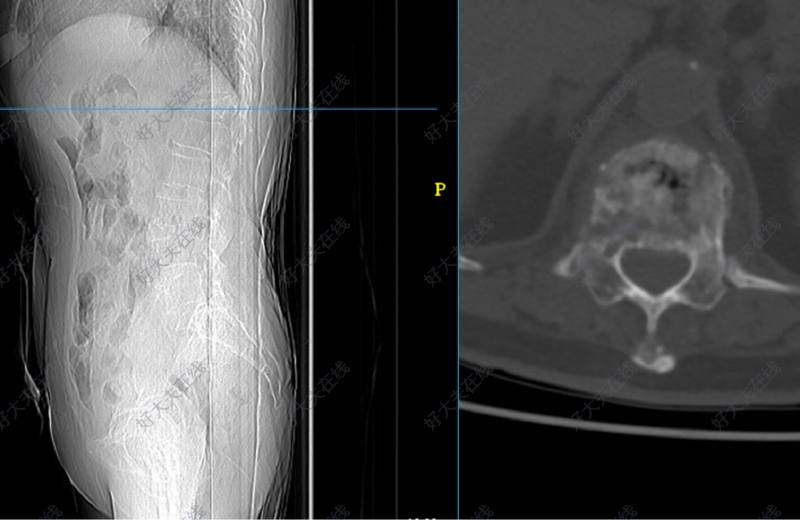

门诊就诊的患者是一位73岁的老年女性,家人搀扶下进来的,头发花白,呈较严重驼背姿态,行动缓慢,独立生活困难。患者诉说2个月前突然出现的腰背部疼痛,没有重视,后来逐渐出现了驼背的症状,最近一周发现下肢走路开始发软,无力,才想着过来医院看。查体时候发现腰背部压痛比较明显,双下肢肌力下降,双侧膝腱反射,跟腱反射亢进。胸腰椎磁共振(MR)提示:胸12(T12)椎体压缩性骨折。同时可以观察到胸椎脊髓受到挤压。后收治病房,进一步行胸腰椎增强磁共振检查,排除了肿瘤,感染等可能性,诊断为胸12椎体压缩性骨折伴脊髓损伤,胸椎后凸畸形。患者既往有高血压和糖尿病的病史。拟定手术方案是胸腰椎后路T10,T11,L1,L2的固定,并对后凸畸形进行矫正。